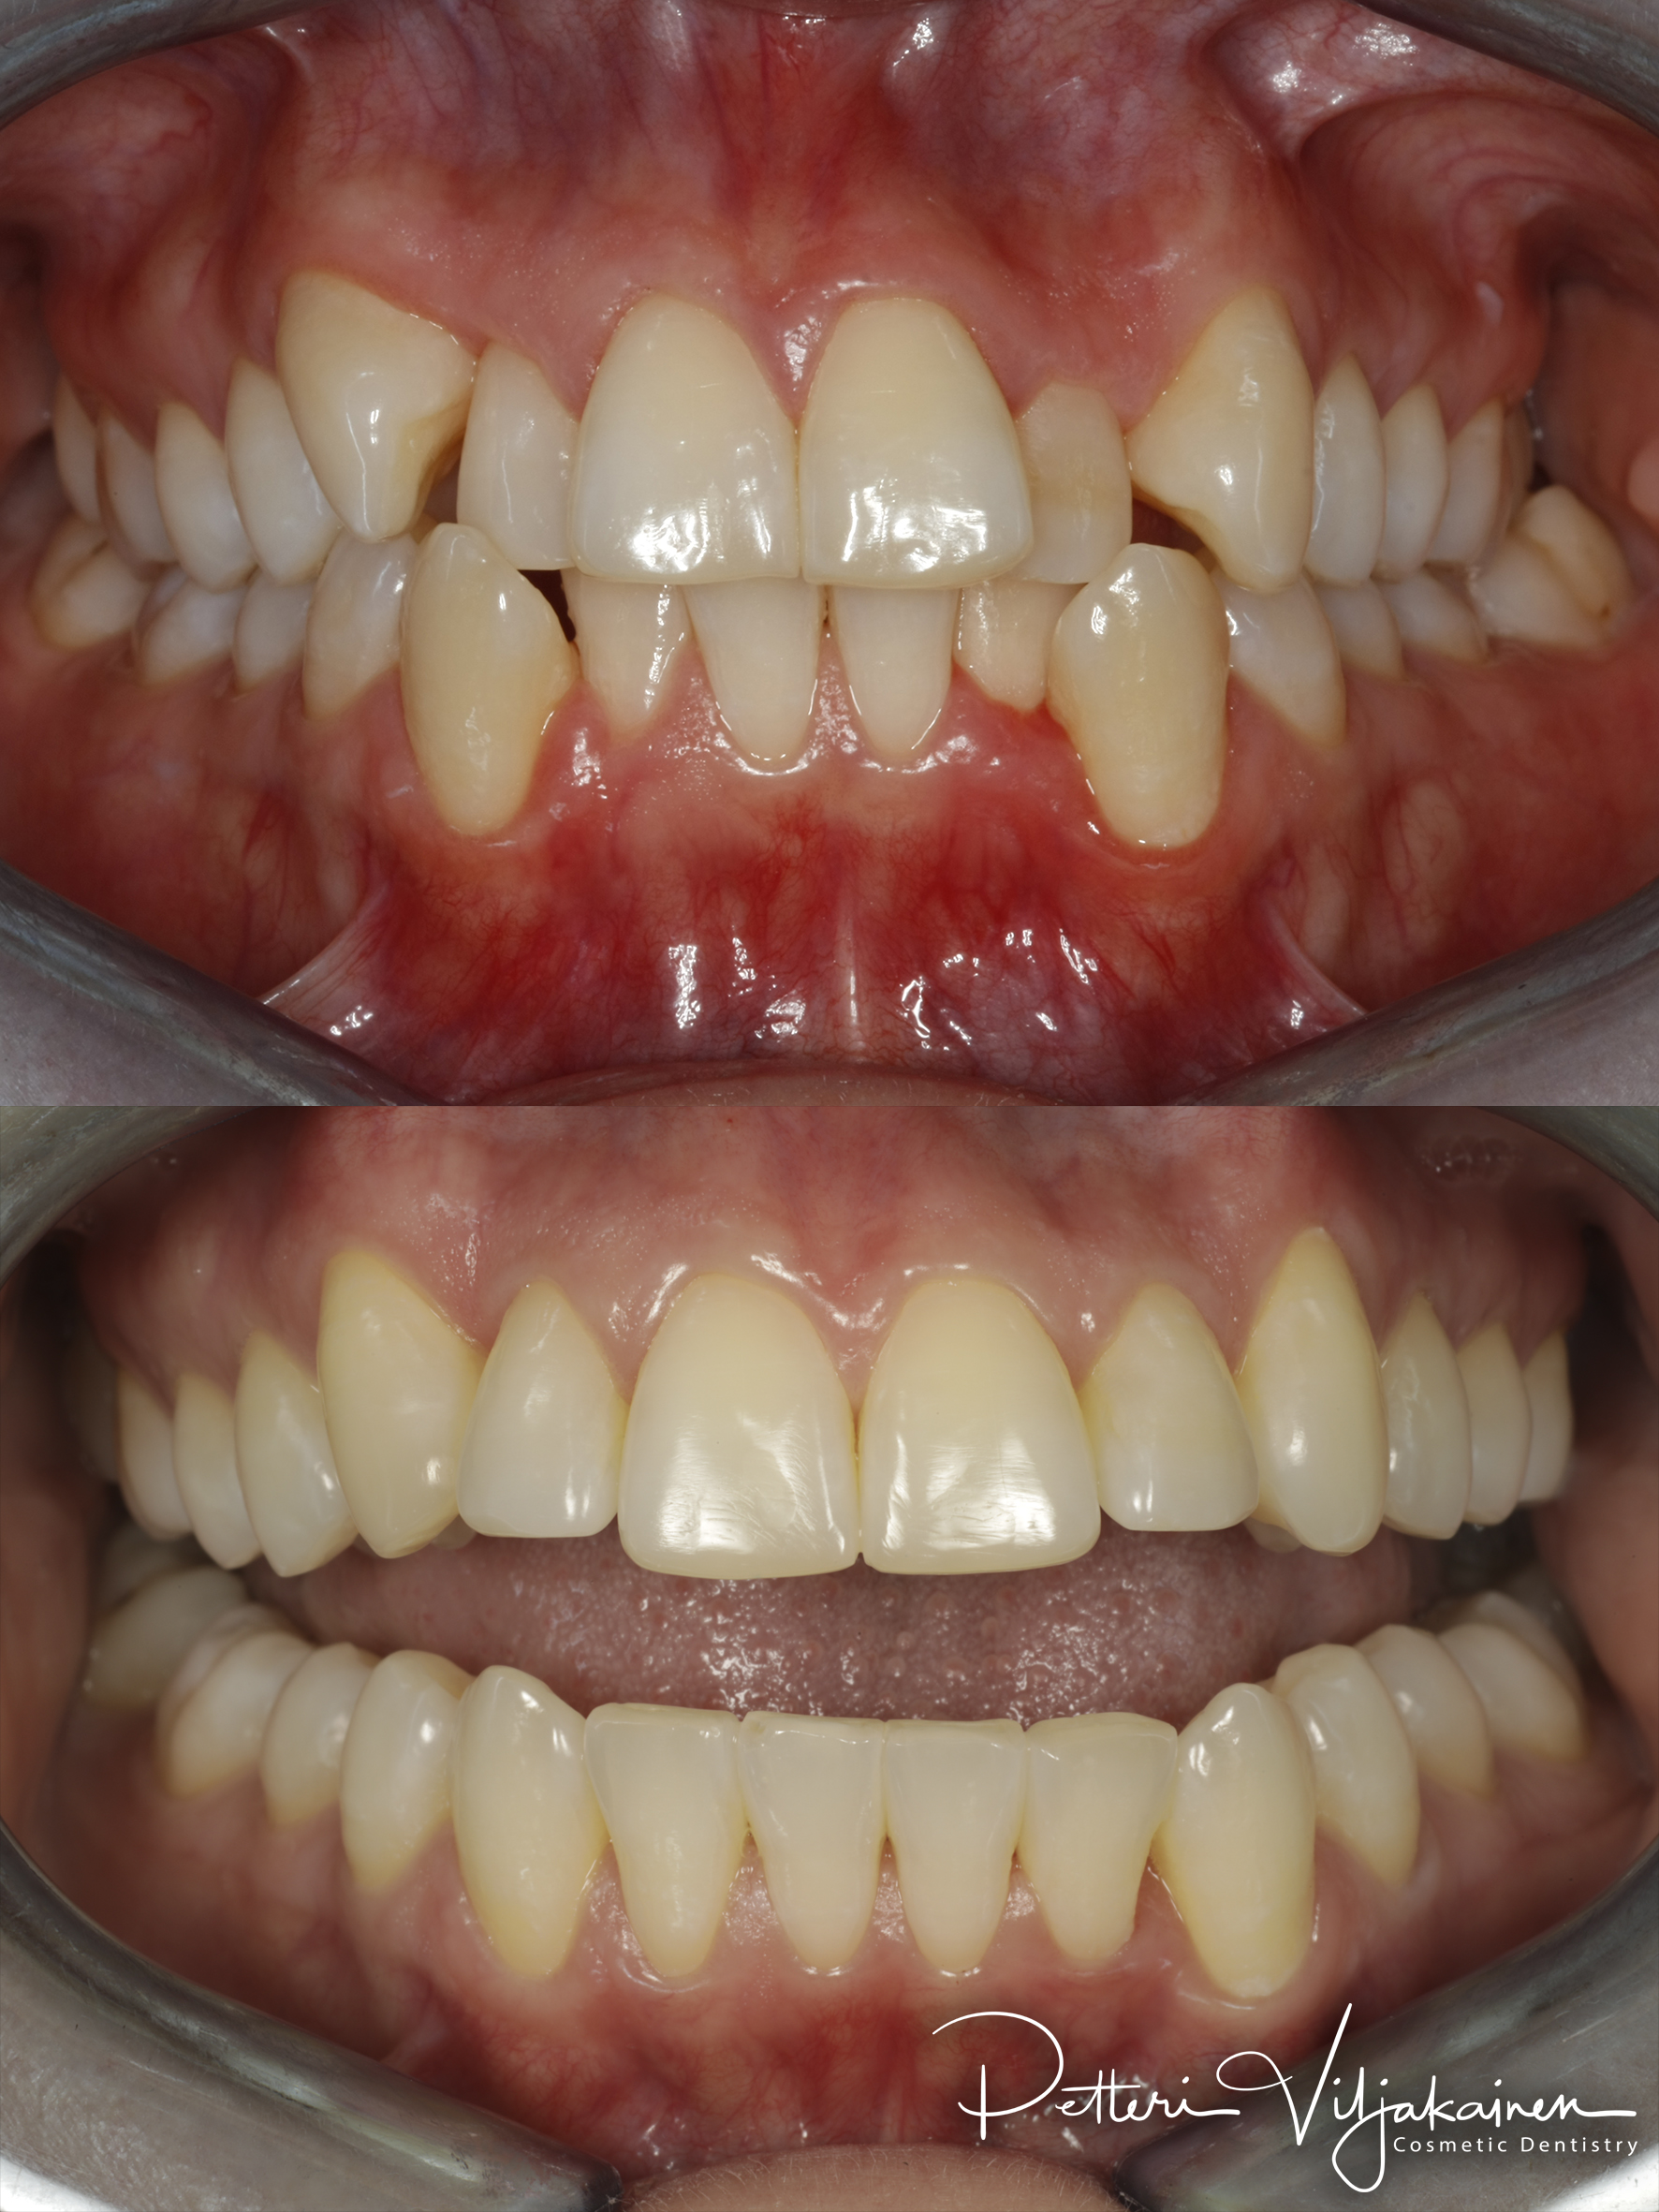

10 kk hoito (Comprehensive). Aavistus esteettistä muovia lisätty yläkulmahampaisiin hoidon jälkeen.